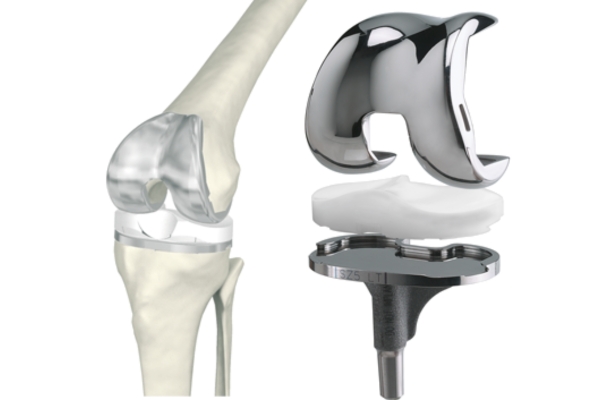

Хирургическое лечение. Часто остеоартроз становится причиной инвалидности. При разрушении сустава назначают частичную или полную его замену. Эндопротезирование - это крайняя мера. После замены сустава механический протез может ломаться. Операция должна быть самым последним выбором для больного человека.

Самое лучшее - остаться со своим суставом и вылечить его. Если игнорировать профилактику и вовремя не начать восстановление сустава, хрящ разрушится окончательно. В итоге, артроз приведет к обнажению кости из-за износа хряща и далее к операции по замене больного сустава.

Как следствие, развивается деформирующий артроз, который в дальнейшем приводит к эндопротезированию.